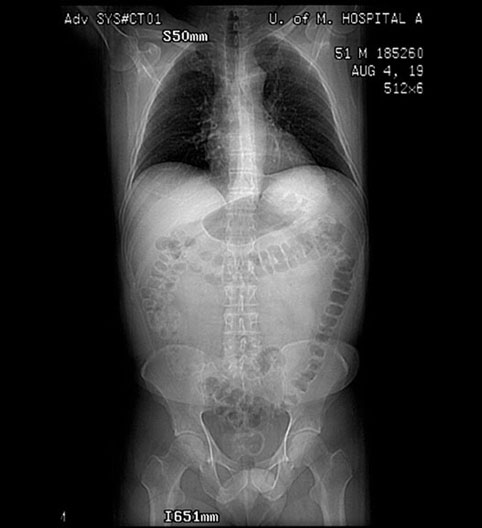

Scout Film of Trunk

Roll mouse over image to display labels.

1. Liver

2. Ascending colon

3. Sigmoid colon

4. Heart

5. Transverse colon

6. Descending colon

7. Small Bowel